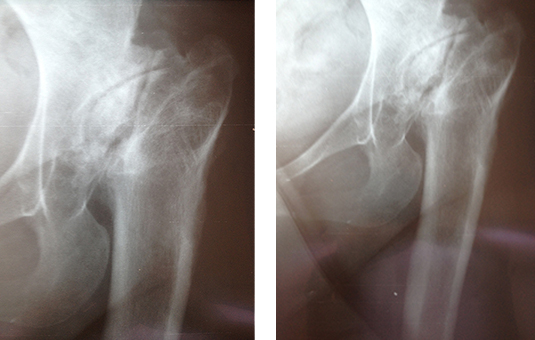

CORRECCIÓN DE AFLOJAMIENTO DE PRÓTESIS 1.PRÓTESIS AFLOJAMIENTO E INFECCIÓN DE VARIOS AÑOS. 2. RETIRO DE LA PRÓTESIS Y COLOCACIÓN DE PERLAS DE ANTIBIÓTICO ENTREVISTA PROGRAMA VIDA ENTREVISTA BDP CANAL 5 ENTREVISTA PIE PLANO ENTREVISTA ZAPATOS CORRECTOS INFILTRACIÓN DE ÁCIDO HYALURONICO EN CADERA